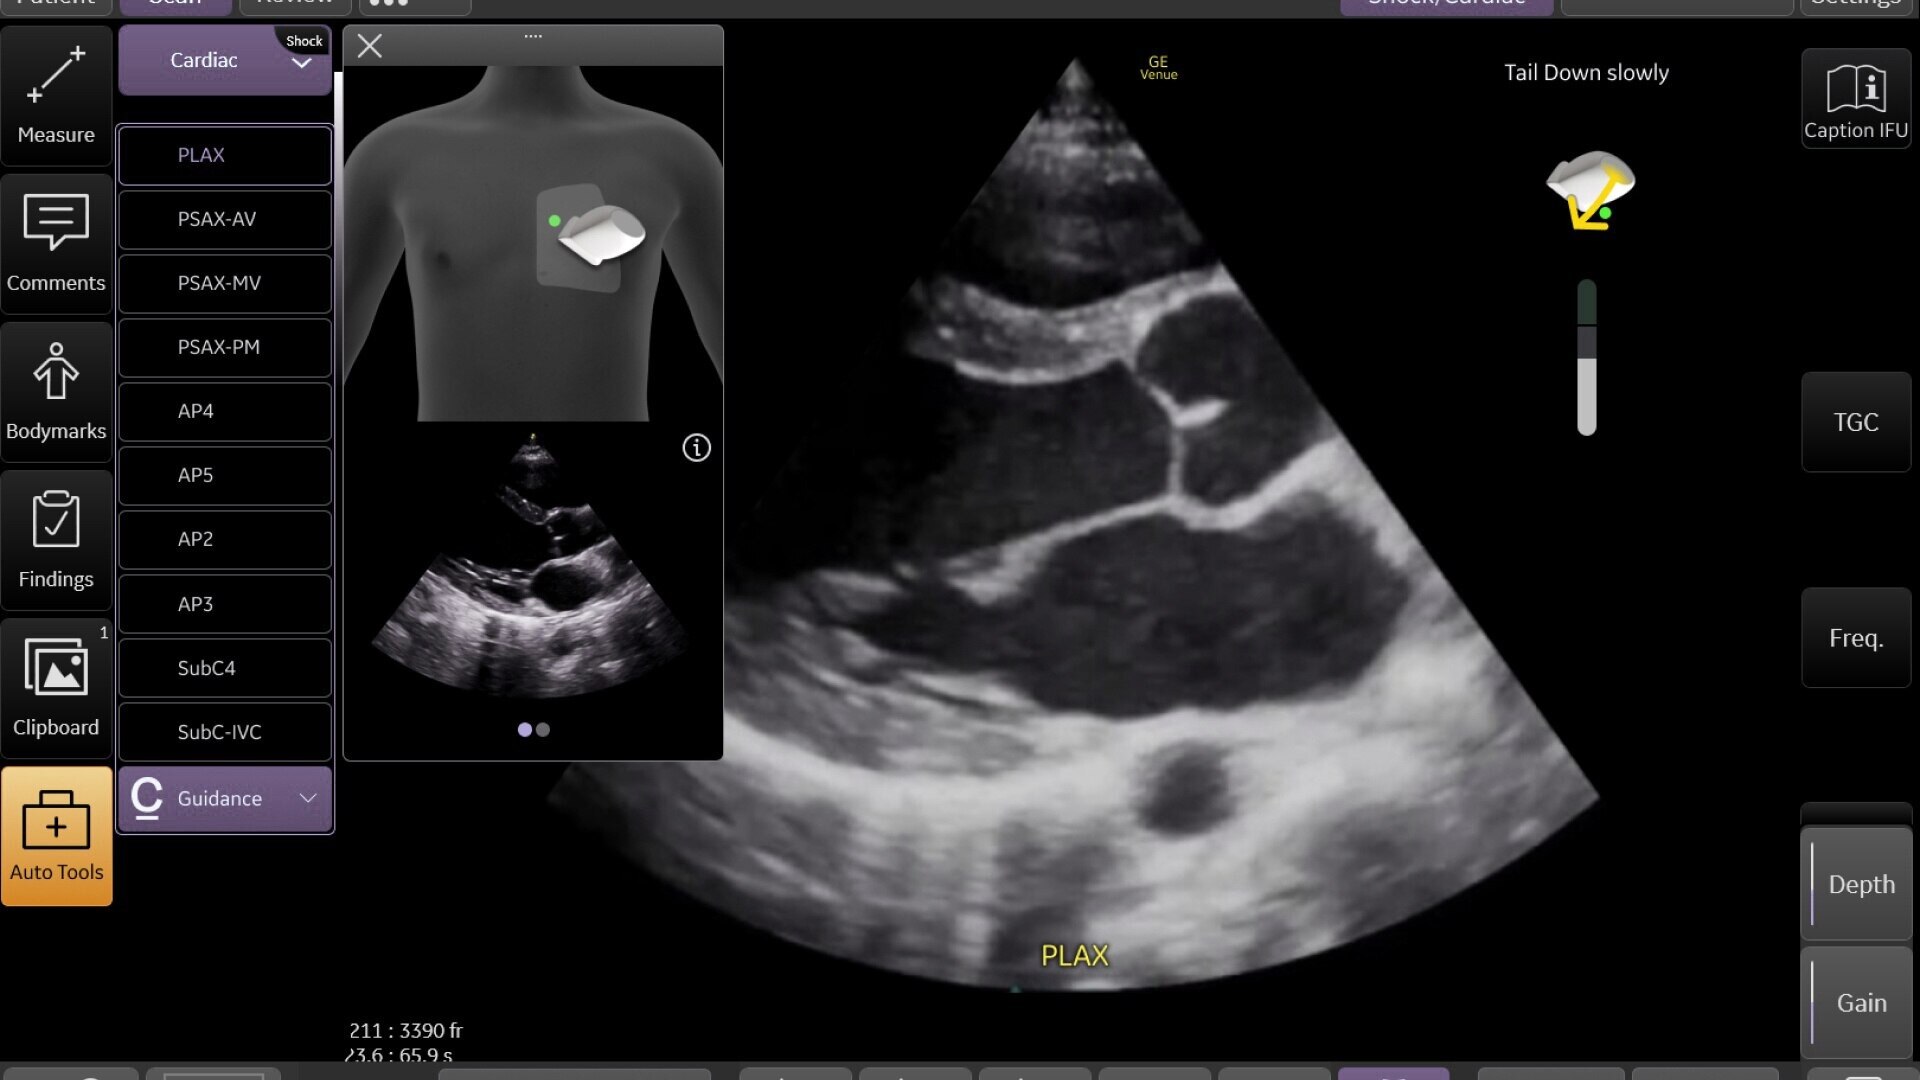

Critical care

Enables on-the-spot visual confirmation, aiding the team in decision-making and collaboration on complex cases.

1-venue-sprint-feature-hero